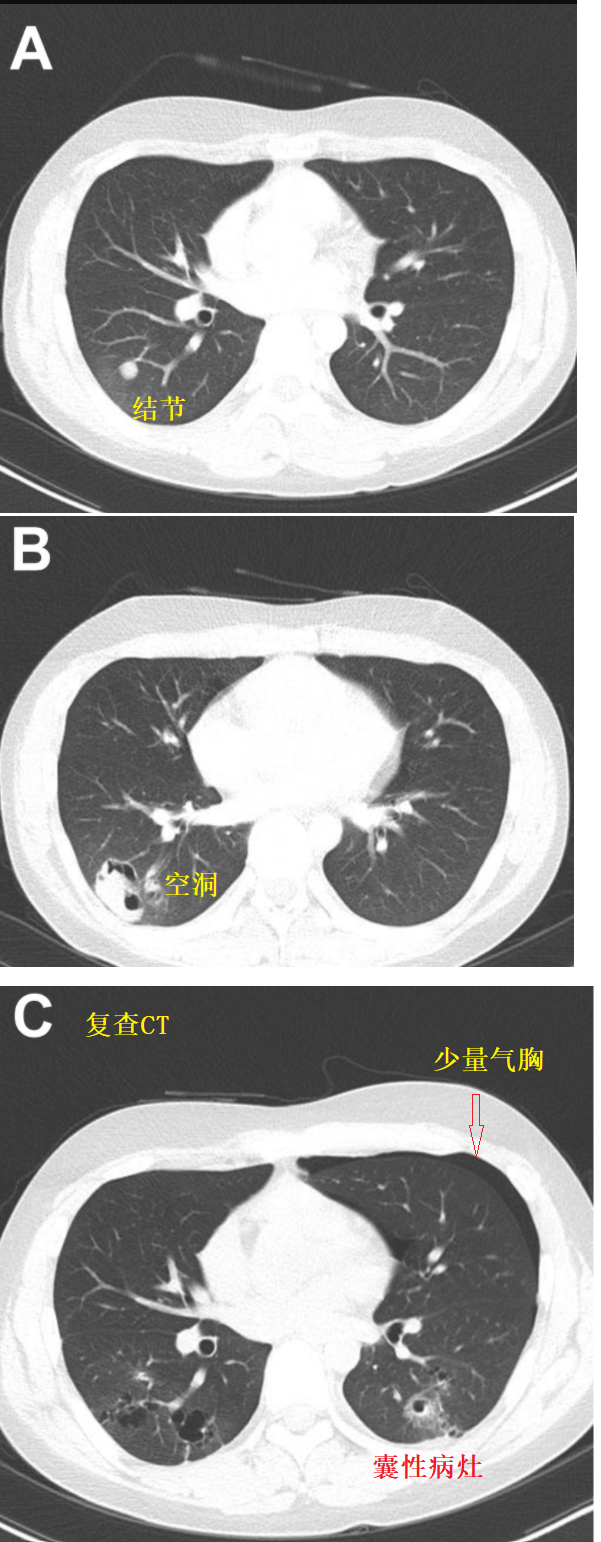

男孩咯血气胸伴空洞找不到原因?皮肤「好」提供了重要线索.